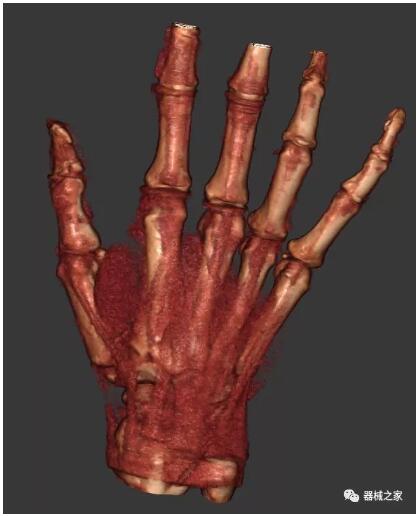

以上介紹的CT均來(lái)自國(guó)外同一家公司,這些CT均配置了可視化軟件,可以進(jìn)行切片、3D重建以及大型CT附帶的所有典型的操作功能。

以下是這些“特立獨(dú)行”的CT所拍出來(lái)的圖像: